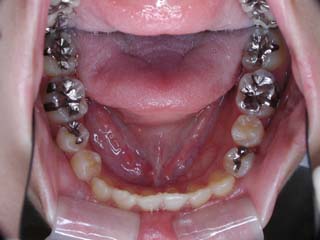

主訴:顎の歪み

診断名:骨格性下顎左方偏位

年齢:24歳

使用した主な装置名:TPB、マルチブラケット装置

抜歯/非抜歯および抜歯部位:非抜歯

治療期間:動的処置1年6か月、経過観察3年

費用の目安:保険適応 自己負担金として30~50万

リスク、副作用:外科手術によるリスク、マルチブラケット治療に伴う歯根吸収など偶発症が発生するリスクがある。

極めて強い側方変位を認めます。前後的・垂直的な問題は見られません。大きなズレであれば、外科的に骨のズレを改善する治療が選択されます。横断的な問題はその他の不正咬合と比較して、解決がかなり難しい事が多いです。治療後の後戻りが頻繁に見られる不正咬合ですので、外科矯正での改善が望ましい場合も多いでしょう。

このケースでは、外科手術は、上顎の傾斜の改善をLeFort1にて、下顎の正中の改善をSSROにて行いました。